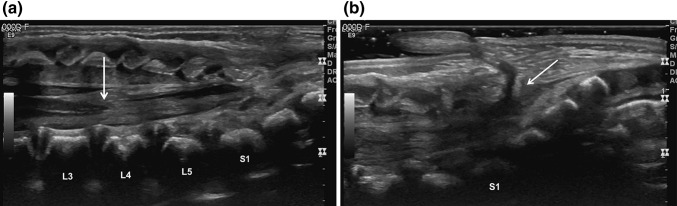

Ultrasound examination of the spine revealed a low lying, tethered cord to the level of L4 (Fig. 2a). A dermal sinus tract was also seen extending from the thecal sac at the level of S1 to the dermal appendage (Fig. 2b) which was also seen at MRI (Fig. 3). Splaying of the posterior elements below the level of S1 was consistent with mild, occult dysraphism (image not shown).

Fig. 2.

a Neonatal spine ultrasound revealing a tethered cord (arrow) at the level of L4. b Dermal sinus tract (arrow) extending from the thecal sac at the level of S1 to the pseudotail